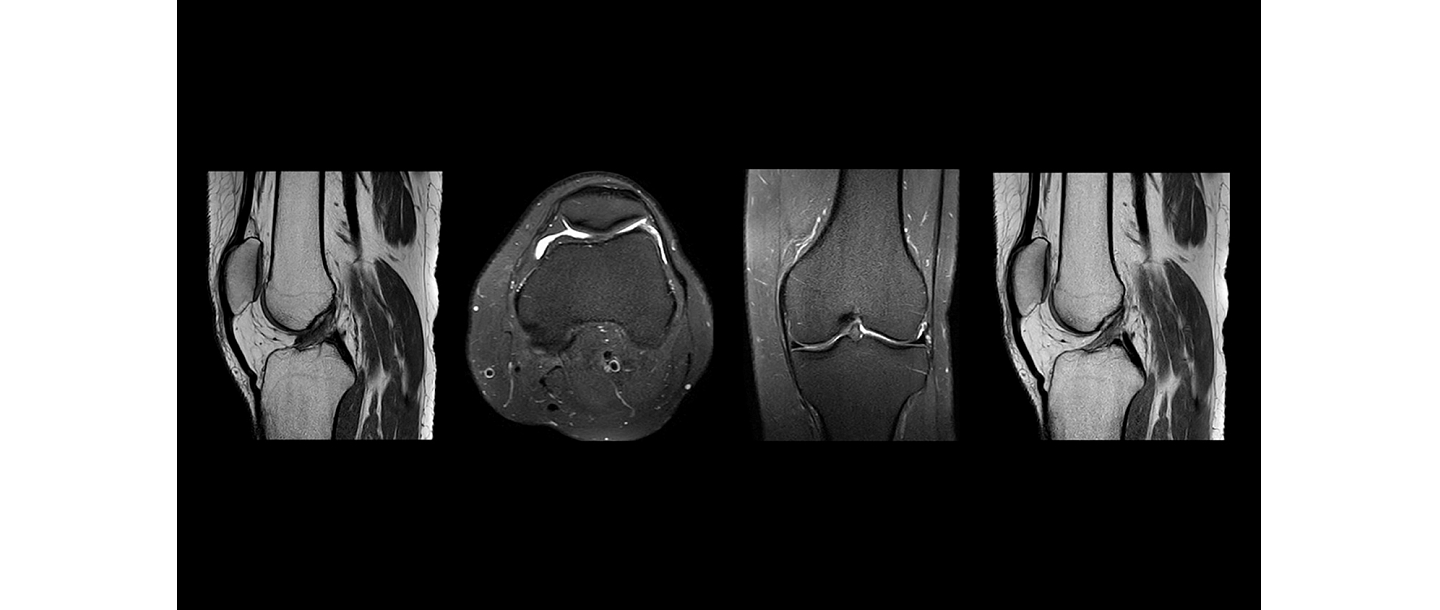

Magnētiskā rezonanse